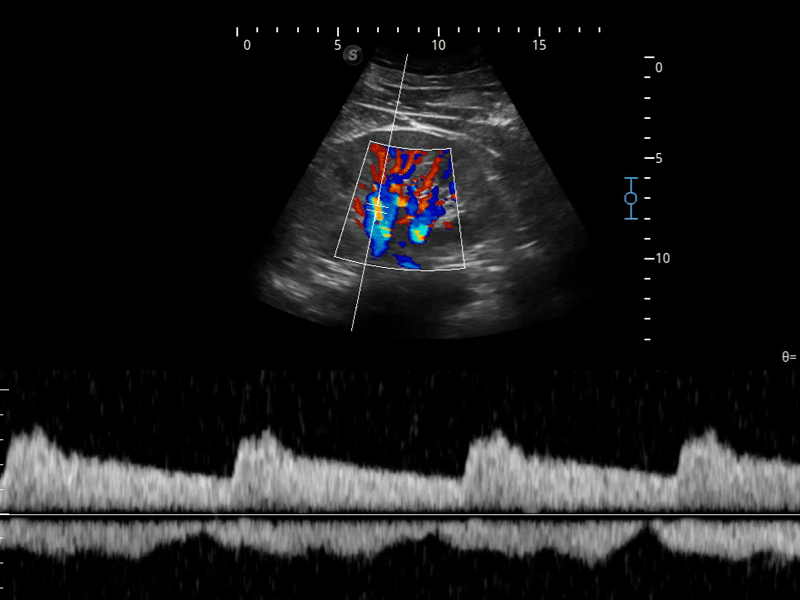

造影成像

造影成像功能和定量分析工具包使医生能够更好的评估血流灌注情况。独特的动态声压控技术有效控制造影剂的声压,保证更长的造影剂持续时间,更好的观察病变灌注的延迟相位。

临床图像